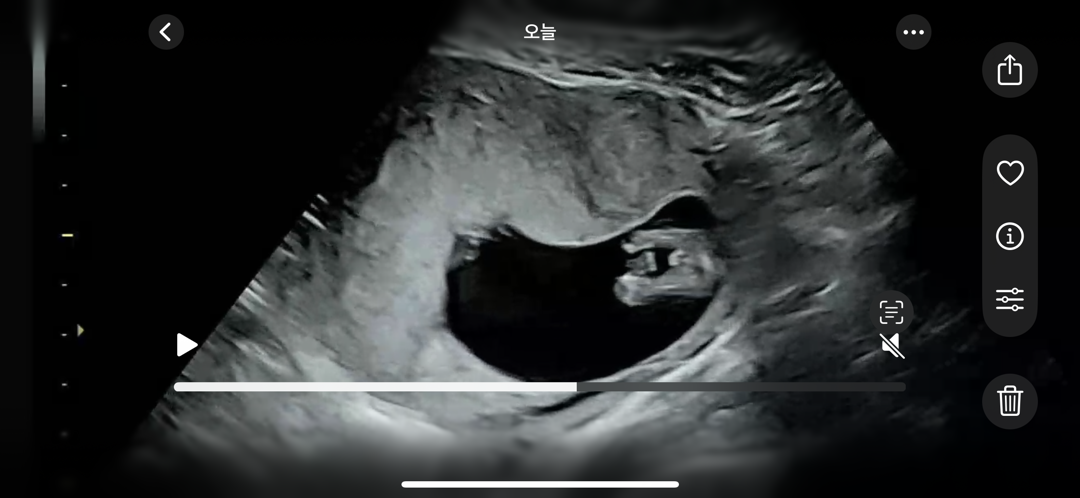

12주5일 이게 다리 맞나요?

다리라면 그 사이에 저것은..?